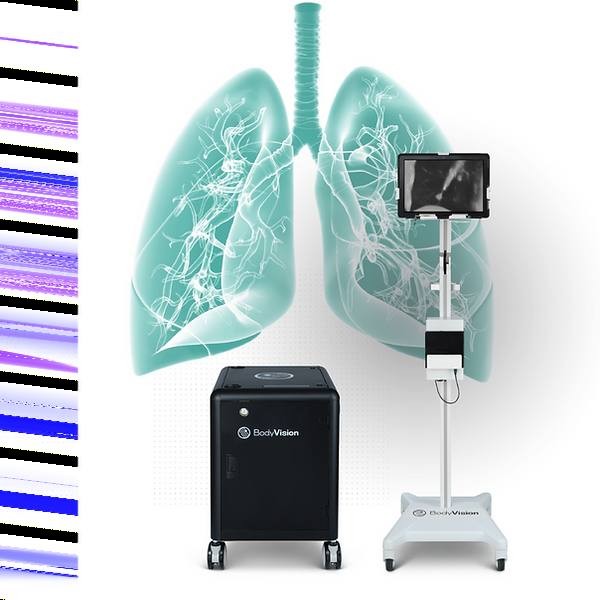

LungVision|Body Vision Medical

项目类型

器械质押区

起投金额

300000USDT

每日释放:1.2

释放周期:160 天

已购: 500

剩余: 0